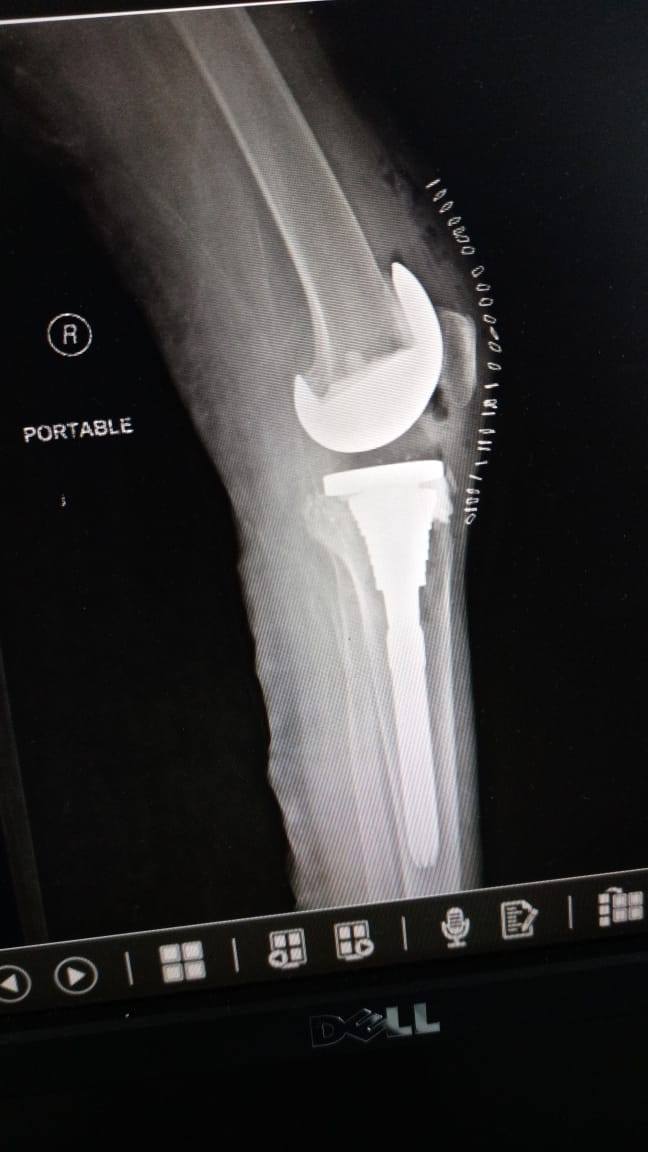

زراعة المفاصل الصناعية ورك و